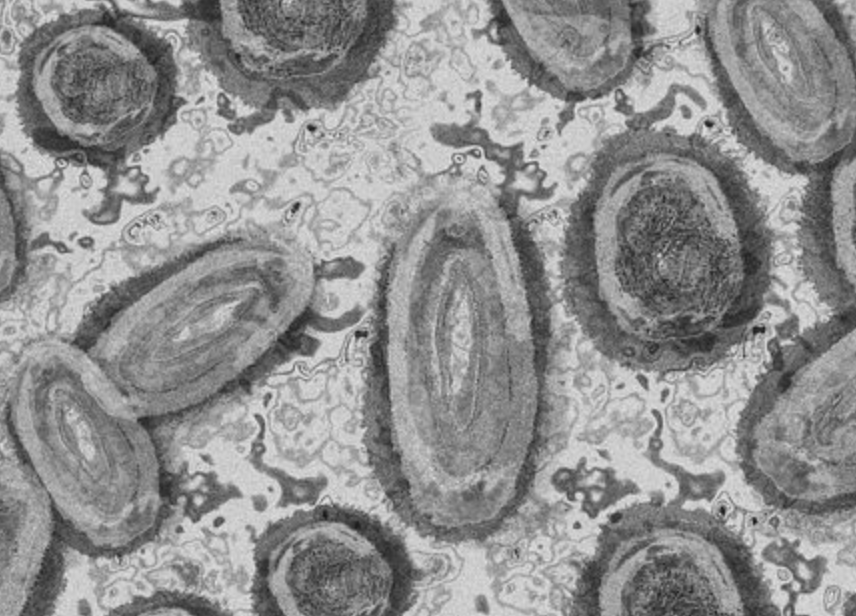

원숭이 두창이란 ?

원숭이두창은 1958년 연구를 위해 원숭이들에게서 수두와 비슷한 질병이 발생하였을 때 처음 발견이 되어, "원숭이두창" 이라는 이름이 붙여졌습니다. 원숭이두창에 감염된 사례에는 두창 퇴치에 노력을 기울이던 1970년 콩고민주공화국에서 처음 보고가 되었으며, 아프리카 지역인 가봉, 나이지리아, 중앙아프리카공화국, 코트디브아르, 카메룬 등 중,서부 아프리카 국가에서 보고되며 풍토병화가 되었습니다.

하지만, 2022년 5월 이후 스페인, 영국, 이탈리아 등 유럽을 중심으로 원숭이 두창은 발생하기 시작해 미국 등 풍토병이 아닌 국가에서 이례적으로 발생하기 되어 국내 유입가능성도 점차 증가하고 있습니다. 대한민국은 2022년 6월 원숭이두창을 2급 감염병으로 보고 있으며, 강화하고 있습니다.